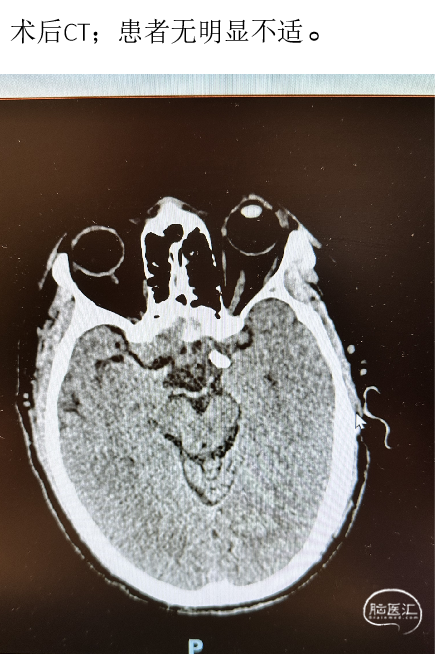

2023-05-12 术后CT

因“突发头痛、呕吐6天”于2023-05-8 12:45 急诊平车入院。神经系统:神志清,精神差,言语流利,双侧额纹对称,双侧瞳孔等大等圆,直径约2.5mm,对光反射灵敏,双侧鼻唇沟对称,口角无歪斜,伸舌居中,颈软无抵抗,四肢肢体肌力检查不配合,肌张力正常,生理反射存在,病理反射未引出。

2023-05-10 术后CT

术后第一天

术后第一天